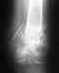

Мне 50 лет. Активно занимаюсь спортом каждый лень, Лыжи беговые, лыжи горные, волейбол, плавание, велосипед, атлетические транажеры( железо). Во время катания на бег лыжах под Одинцово с горки вылетел на лед и грохнулся , рука оказалась за спиной. По снимку перелом без смещения плечевой кости, но главное порваны связки в передней части плеча и бицепс. 2\3 бицепса, если сравнивать с правой рукой вообще отсутствуют. Хочу продолжать заниматься спортом. Подскажите что делать. Нужна операция? Сшивают ли бицепсы и плечевые связки и где?